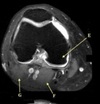

Perfectly

11

Q

What is letter A?

A

ANTERIOR LABRUM

How well did you know this?

1

Not at all

2

3

4